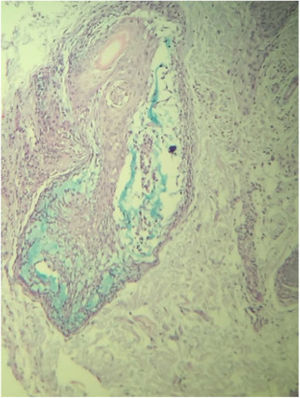

A routine anatomopathological examination (Hematoxylin & eosin staining) reveals preserved epidermis. Dermis presents some hair follicles containing fibromyxoid stroma and mixed pattern inflammatory cells (Fig. 2). Alcian Blue stain reveals built-up mucin in the outer root sheath of the hair follicle (Fig. 3).

Histopathology is essential for diagnosis since it shows mucin deposits on the outer root sheath of the hair follicle, in addition to inflammatory infiltrates composed of lymphocytes, macrophages and eosinophils with folliculotropic lymphocytes. The benign form is determined by the extension of the eosinophilic inflammatory infiltrate and significant mucinous alterations in the follicular epithelium.5 Similar findings were observed in the patient‘s results. Presence of epidermotropic lymphocytes and dense perifollicular infiltrate of atypical cells suggest a malignant form of the condition; however, no evidence of it was found in the studied patient.